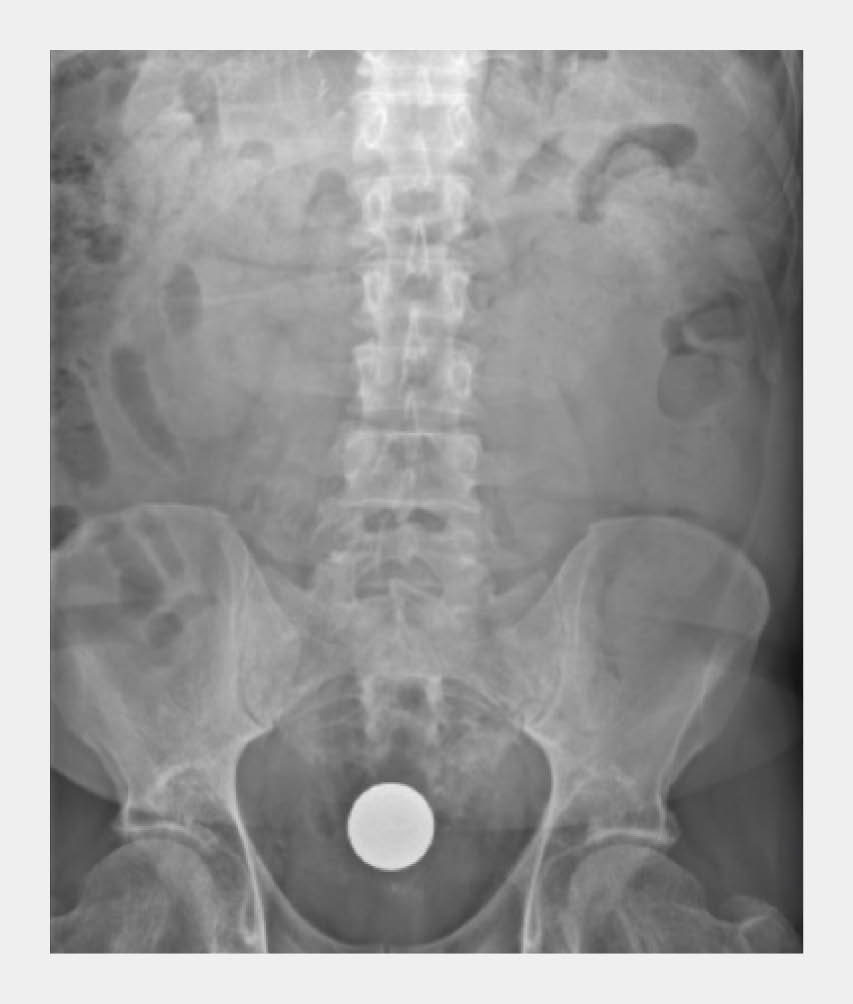

Bij lichamelijk onderzoek zagen we een niet-zieke man. De vitale parameters waren niet-afwijkend, en de buik was soepel zonder druk- of loslaatpijn. Bij rectaal toucher was de ijzeren bal palpabel, maar niet goed te manipuleren. Er werd een buikoverzichtsfoto gemaakt, waarbij de ijzeren bal duidelijk zichtbaar was in het rectum; er waren geen tekenen van een ileus (figuur 1).

Figuur 1

IJzeren bal in rectum van patiënt A

Anterieur-posterieure buikoverzichtsfoto

Figuur 1 | IJzeren bal in rectum van patiënt A | Anterieur-posterieure buikoverzichtsfoto